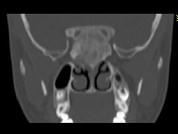

女,17岁,鼻阻塞、头痛两年.如图所示符合筛骨病变最可能的诊断是 ( )

• A.成骨肉瘤

• B.骨瘤

• C.骨化性纤维瘤

• D.软骨瘤

• E.纤维异常增殖症

答案: C